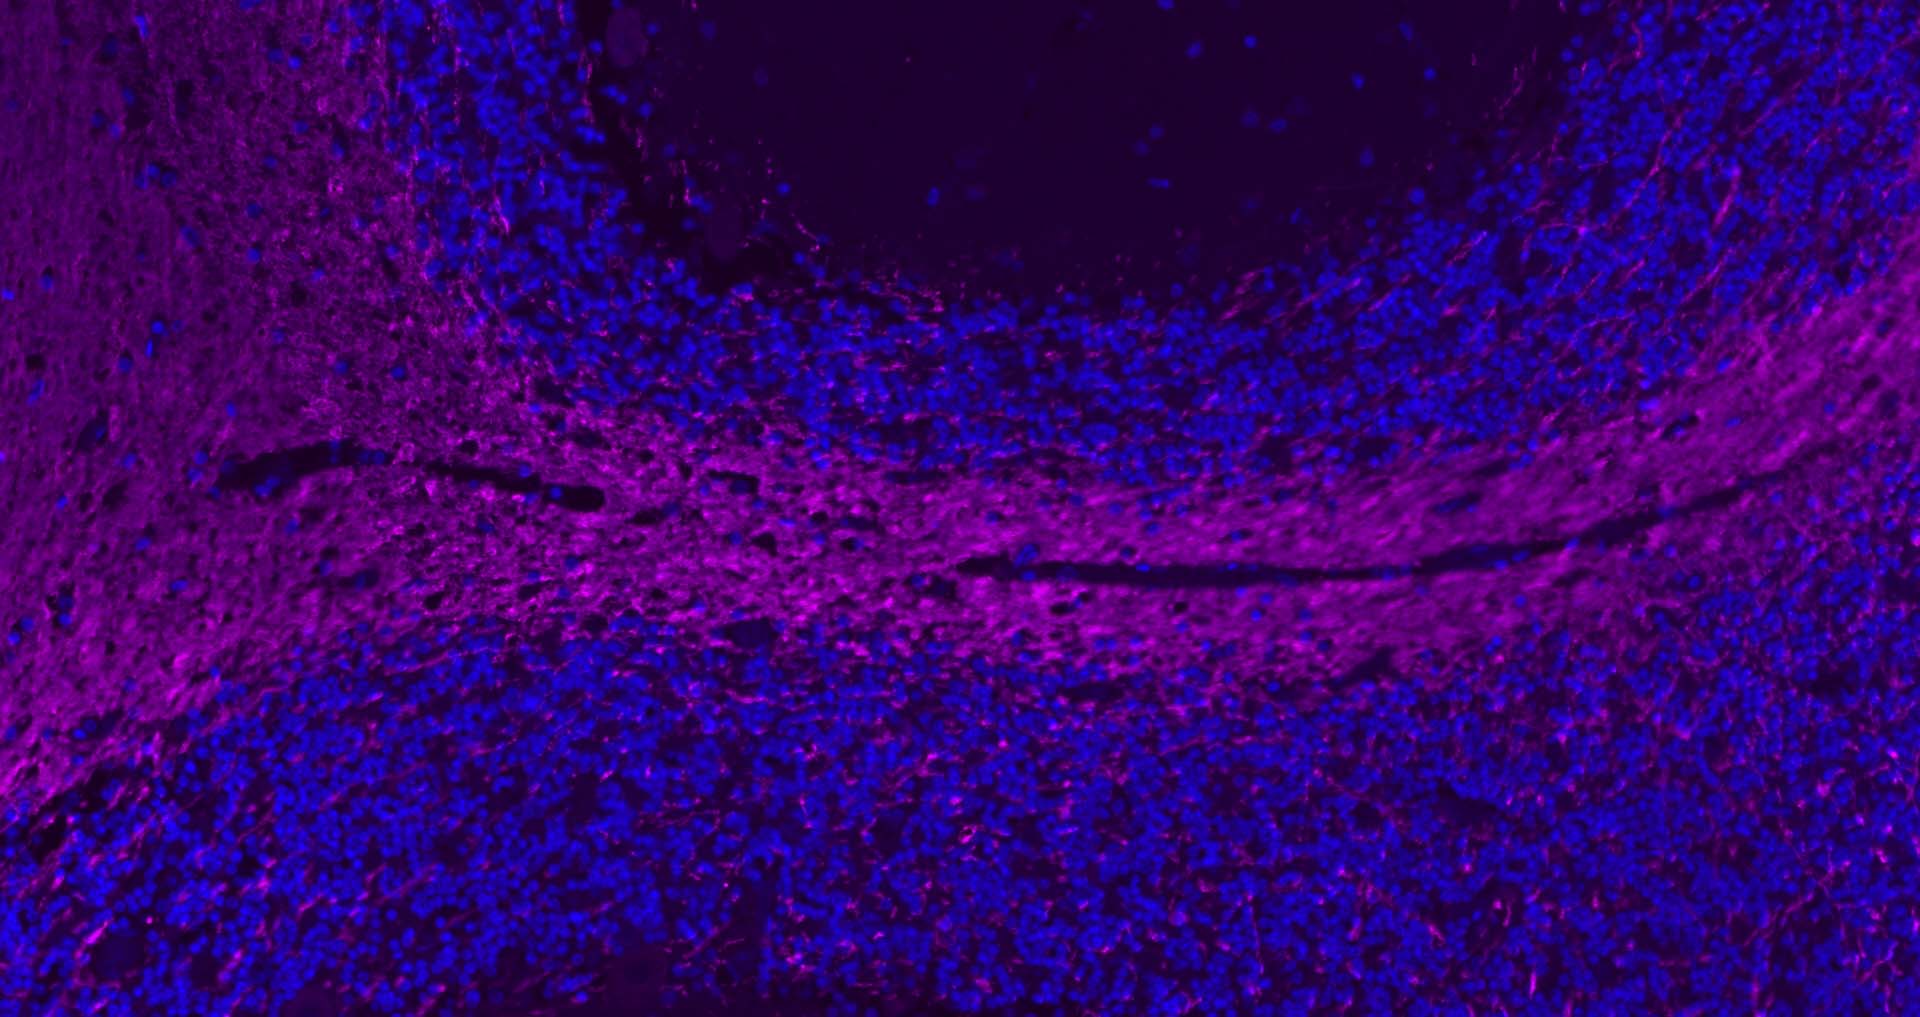

Paraformaldehyde-fixed, paraffin embedded Mouse Cerebellum; Antigen retrieval by boiling in sodium citrate buffer (pH6.0) for 15 min; Antibody incubation with MBP Polyclonal Antibody, Unconjugated (bs-24827R) at 1:200 overnight at 4°C. Followed by conjugated Goat Anti-Rabbit IgG antibody (Purple, bs-0295D-Cy5), DAPI (blue, C02-04002) was used to stain the cell nuclei.

Paraformaldehyde-fixed, paraffin embedded Mouse Cerebrum; Antigen retrieval by boiling in sodium citrate buffer (pH6.0) for 15 min; Antibody incubation with MBP Polyclonal Antibody, Unconjugated (bs-24827R) at 1:200 overnight at 4°C. Followed by conjugated Goat Anti-Rabbit IgG antibody (Purple, bs-0295D-Cy5), DAPI (blue, C02-04002) was used to stain the cell nuclei.